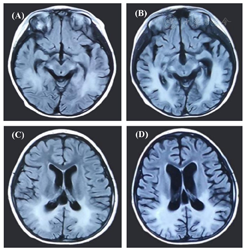

影像学检查:患者1:头颅MRI示脑干、双侧基底节、丘脑、双侧侧脑室后角旁、胼胝体多发异常信号,Loes评分7分。患者2:HSCT前,头颅MRI示病变累及双侧半卵圆中心、侧脑室三角区及枕角周围脑白质及双侧丘脑、胼胝体后部及压部、双侧大脑脚、脑桥及延髓皮质脊髓束区,Loes评分9分;HSCT后头颅MRI示颅内异常信号范围较前增多(图1)。患者3:头颅MRI示双侧侧脑室后角旁可见较对称斑片状异常信号,蝶翼样分布;左额叶可见线样异常信号,Loes评分4分。

注:HSCT:造血干细胞移植;(A)(C)为HSCT治疗前患者2的头颅MRI表现,病变累及双侧半卵圆中心、侧脑室体后周围、侧脑室三角区及枕角周围脑白质及双侧丘脑、胼胝体后部及压部、双侧大脑脚、脑桥及延髓皮质脊髓束区;(B)(D)为HSCT治疗后患者2的头颅MRI表现,颅内异常信号范围较前增多